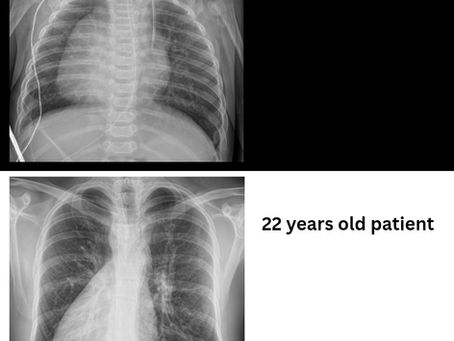

🫀Two Hearts on the Right Side

Within a single week, our team treated two patients with dextrocardia — a rare congenital condition in which the heart is located on the right side of the chest. In both cases, this was accompanied by situs ambiguous, an even rarer anatomical variation. These are the kinds of cases a cardiac surgeon may never encounter in an entire career — yet they presented twice within one week at our center.